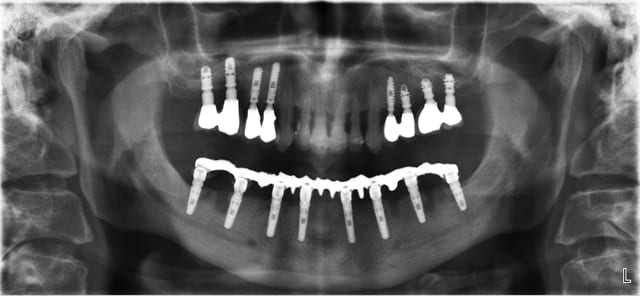

Quand je fais des EMCI totale sur 6 à 8 implants avec appui osseux

je pose les implants puis les piliers qui sont l’équivalent de couronnes télescopiques, et le bridge à armature métallique sans scellement ni vis, dans la même séance

Un avec bridge immédiat c'est plus marrant et fonctionnel de suite. En haut j'ai fait comme toi et sans guide radio.

Je précise qu'avec cette technique j'ai pu adapter le même principe que Beotien à un système vissé.

Ce cas est visible sur le site de Positdental.